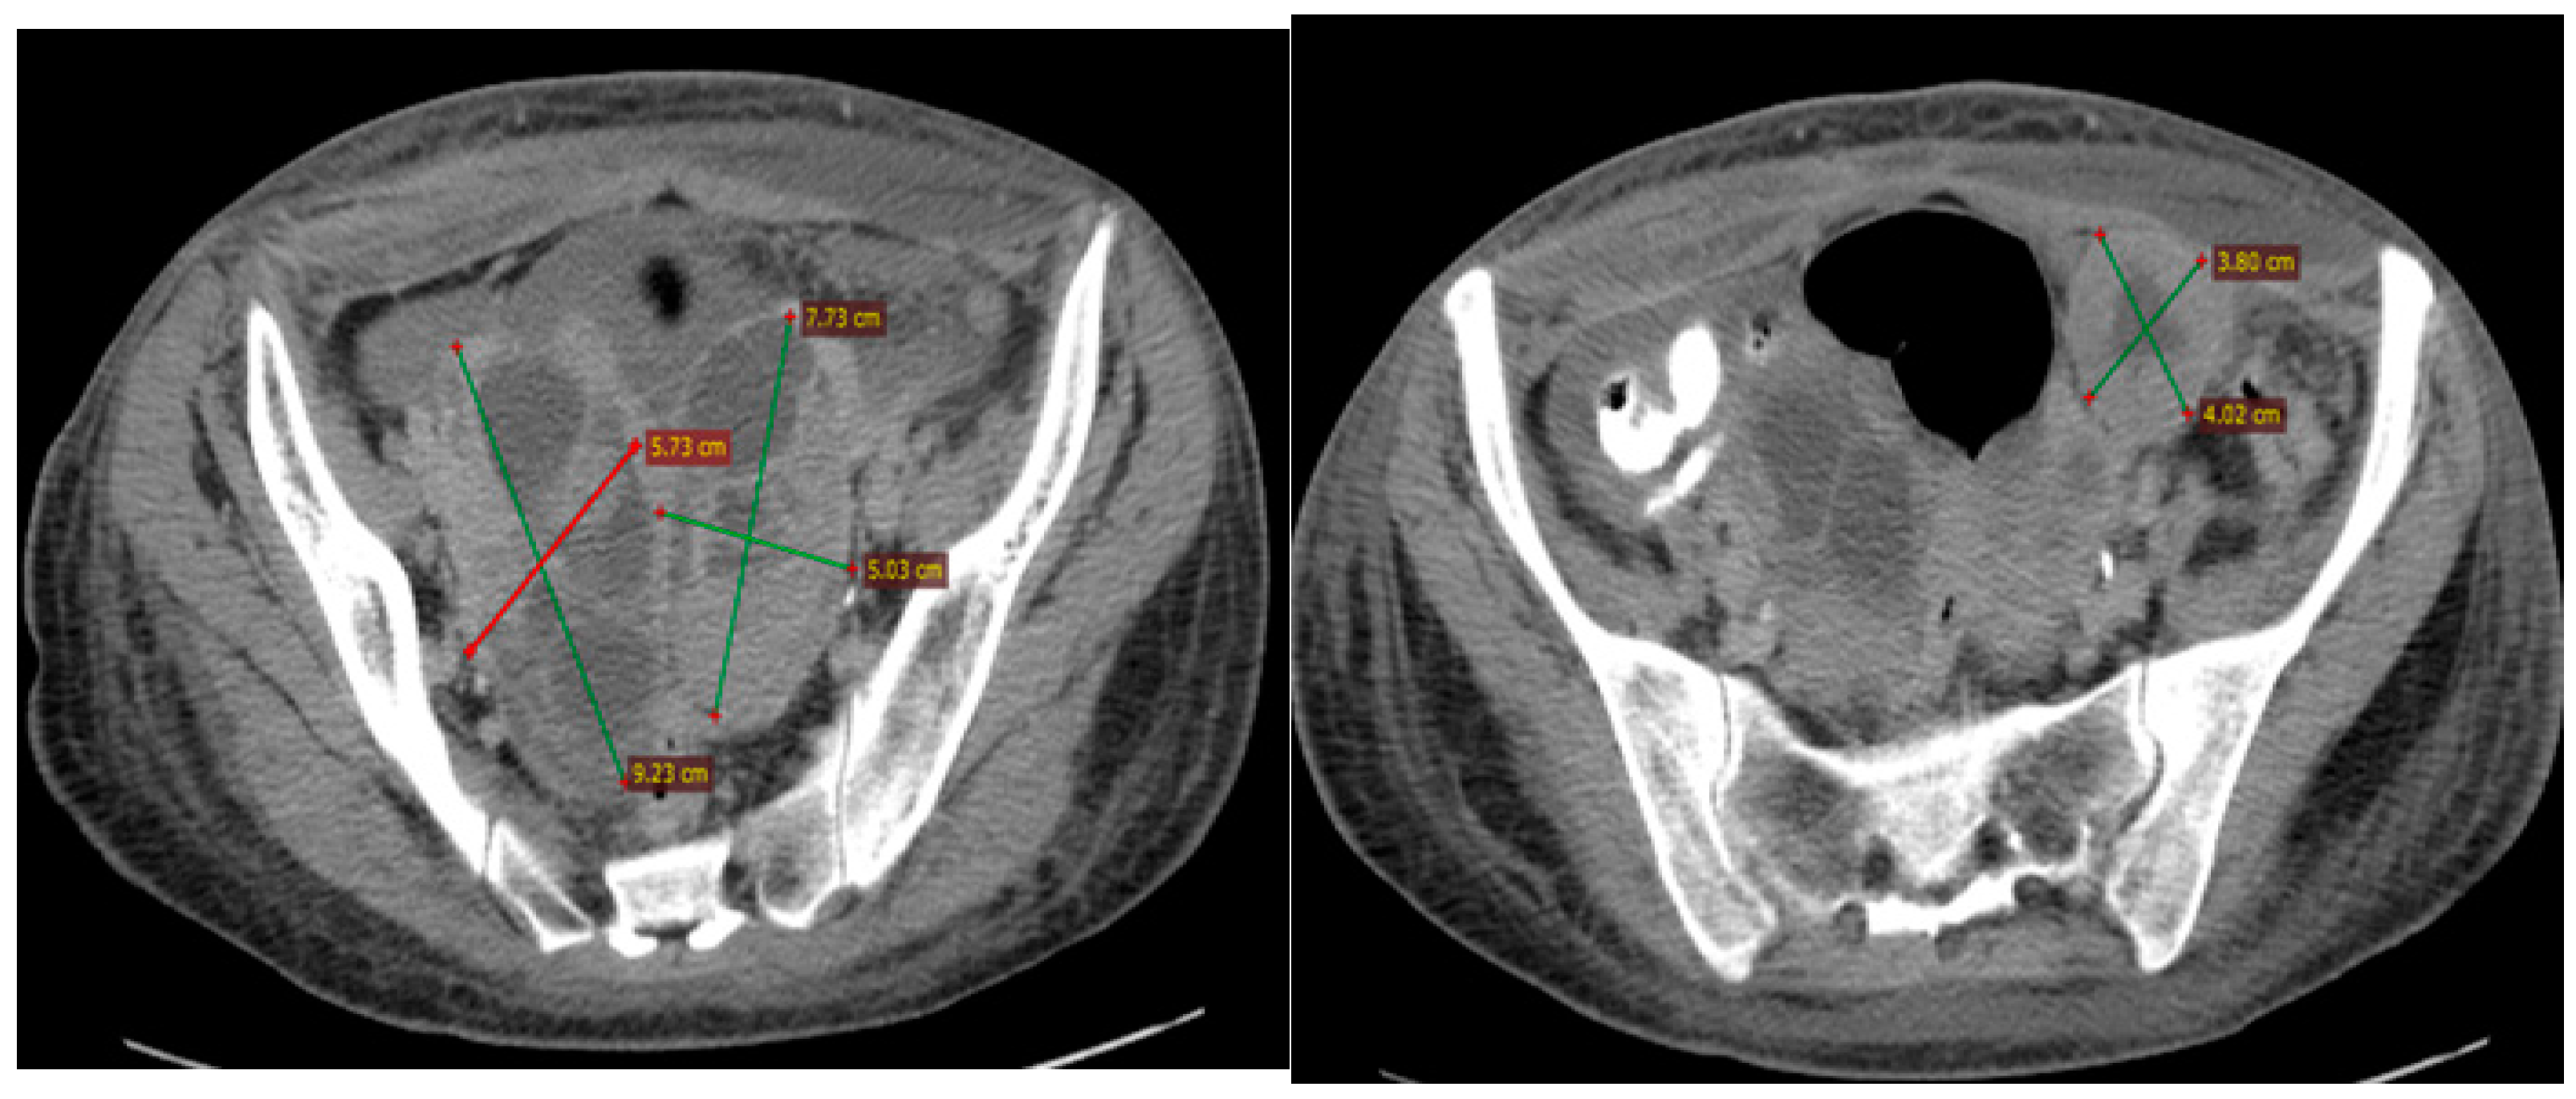

In June 2015, the patient was admitted to the Iasi Regional Oncology Institute (IRO). A computed tomography (CT) scan of the thorax, abdomen, and pelvis showed tumors in both ovaries (right, 92/57/65 mm; left, 70/50/72 mm) and one 40/38 mm left iliac adenopathy (Figure 1).

Figure 1.

The baseline CT scan of the pelvis from June 2016 showing the ovarian tumors and the lymph node in the left iliac fossa.

Between June and October 2015, three cycles of Carboplatin (AUC 5) and Paclitaxel (175 mg/m2) were administered every 3 weeks, followed by two cycles of Carboplatin (AUC 5) alone due to poor clinical tolerance (asthenia) and hematological toxicity (thrombocytopenia grade 1 and anemia grade 2). A post-chemotherapy CT scan described a partial response according to the Response Evaluation Criteria in Solid Tumors (RECIST 1.1): tumor in the right ovary, 52/19/44 mm; tumor in the left ovary, 42/27/37 mm; no ascites; and one peritoneal nodule of 11/10 mm (Figure 2).

Figure 2.

The first follow-up (CT scan of the pelvis, October 2015) showing partial response to treatment.